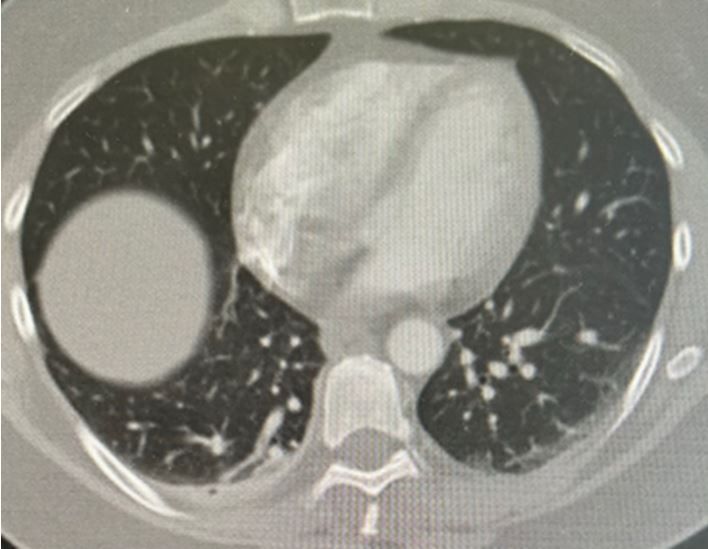

A woman in her mid-50s arrives at the ED for suspected anaphylaxis; SOB has not responded to epinephrine and steroids. Does the CT scan suggest a Dx?

Imaging